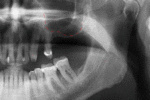

قبل زراعة الأسنان، يطلب من المريض اجراء فحص تصوير للأسنان، وعادة يطلب اجراء صورة خاصة (صورة أشعة بانوراما للأسنان) أو حتى فحص التصوير المقطعي المحوسب (CT)، للكشف والتشخيص عن حالات الأسنان التي ليس بالامكان رؤيتها من خلال الفحص الاعتيادي.